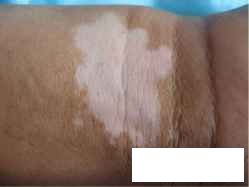

贵州哪家医院治病白癜风治的好?专家提醒:白癜风患者要重视自己的疾病治疗工作,避免全身出现大面积白斑,引发更为严重的后果发生。白癜风是由于素细胞的缺失导致的色素脱失性皮肤病,夏季患者一定要避免紫外线强烈照射,以免大量的黑素细胞缺失或受损,引发皮肤癌发作。